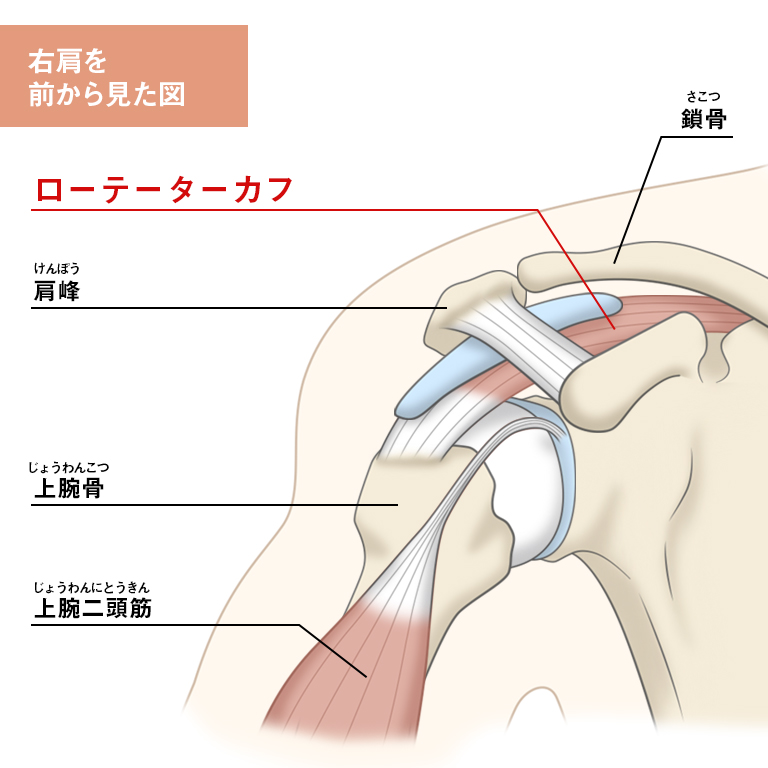

インピンジメント症候群 Mcdavid サポータ ブランドのマクダビッド オフィシャルサイト